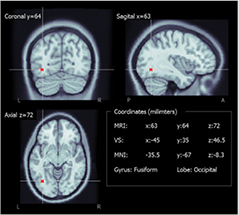

3.1. Detection of the ROI

To evaluate the selected ROIs resulting from the first stage in the volume reconstruction model, the coordinates of the central virtual sensor were normalized into MNI space using Brainstorm software (figure 4) and the gyrus and lobes were obtained for this position in the normalized atlas (table 2). The central VSs of the nine subjects matched the lobe where seizures had been generated (table 1).

Figure 4. Example of localization of the middle virtual sensor (in red) in the warped anatomy and the posterior MNI transformation.